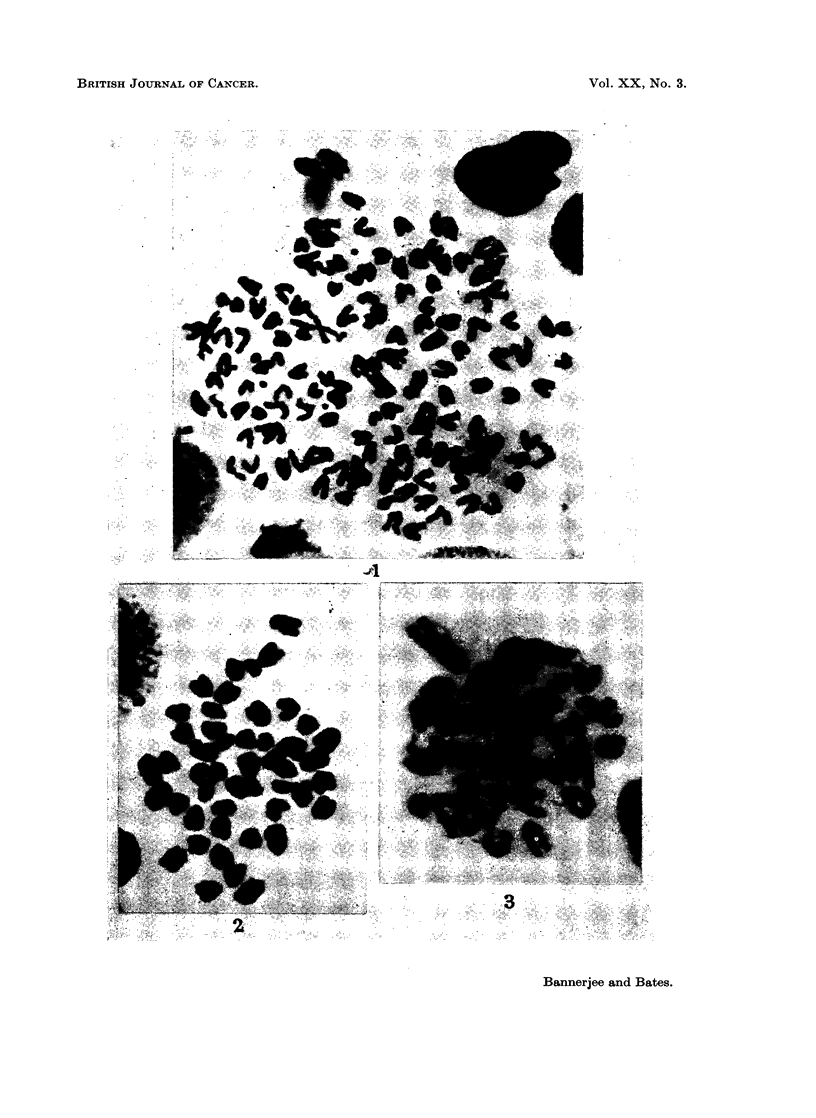

- BANERJEE M. R., DEOME K. B. Chromosomes in normal, preneoplastics, and neoplastic tissues of the mammary glands of C3H/Crgl female mice. Cancer Res. 1963 May;23:546–550. [PubMed] [Google Scholar]